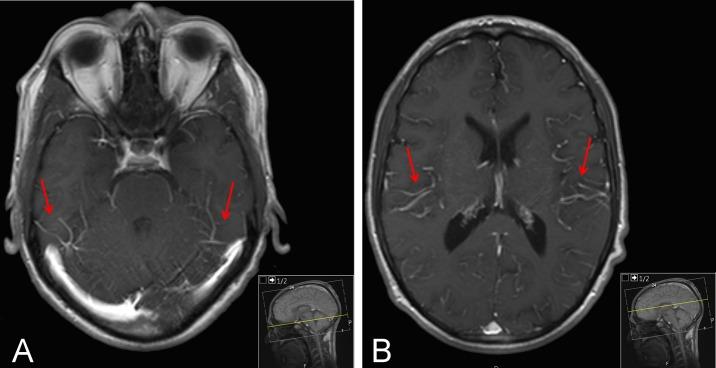

A 29-year-old man complained of a 2-day history of frontal headache and new-onset fever but no other symptoms. Two months prior to admission, he underwent his third kidney transplantation. Clinical and laboratory examinations were unremarkable. Brain MRI showed a meningeal irritation consistent with viral meningitis. A diagnosis of cryptococcal meningitis and fungaemia was made after detection of a remarkably high and visible load of in the cerebrospinal fluid.

一名29岁男性主诉有2天的前额头痛和新发发热史,但无其他症状。入院前两个月,他接受了第三次肾脏移植。临床和实验室检查无异常。脑部磁共振成像显示脑膜刺激征,符合病毒性脑膜炎表现。脑脊液中检测到极高且明显的隐球菌载量后,确诊为隐球菌性脑膜炎和真菌血症。